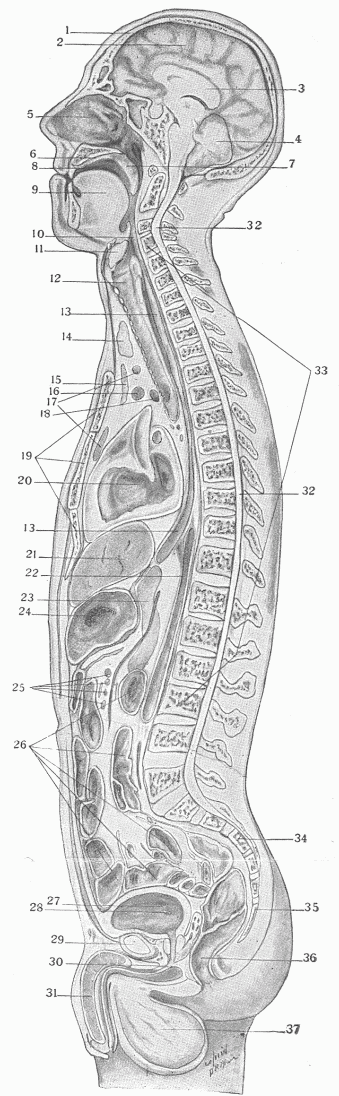

Fig. 8.—A Longitudinal Section Through The Middle Of The Body Showing The External And Internal Surfaces And The Organs.

1. The skull.

2. The brain, showing the convolutions of the gray exterior in which the nerve cells are most numerous.

3. The white matter in the interior of the brain formed of nerve fibres which connect the various parts of this.

4. The small brain or cerebellum.

5. The interior of the nose. Notice the nearness of the upper part of this cavity to the brain.

6. The hard or bony palate forming the roof of the mouth.

7. The soft palate which hangs as a curtain between the mouth and the pharynx.

8. The mouth cavity.

9. The tongue.

10. The beginning of the gullet or oesophagus.

11. The larynx.

12. The windpipe or trachea.

13. The oesophagus.

14. The thyroid gland.

15. The thymus gland or sweetbread.

16. The large vein, vena cava, which conveys the blood from the brain and upper body into the heart.

17-25. Lymph nodes; 17, of the neck; 25, of the abdomen.

18. Cross section of the arch of the aorta or main artery of the body after it leaves the heart.

19. The sternum or breast bone.

20. The cavity of the heart.

21. The liver.

22. The descending aorta at the back of the abdominal cavity.

23. The pancreas.

24. The stomach.

26. Cross section of the intestines.

27. The urinary bladder.

28. The entrance into this of the ureter or canal from the kidney.

29. Cross sections of the pubic bone.

30. The canal of the urethra leading into the bladder.

31. The penis.

32. The spinal cord.

33. The bones composing the spinal column.

34. The sacrum. The space between this and No. 29 is the pelvis.

35. The coccyx or extremity of the back bone.

36. The rectum.

37. The testicles.

The genito-urinary surface is the smallest of the surfaces. In the male (Fig. 8,—27, 28, 30) this communicates with the general external surface by the small opening at the extremity of the penis, and in the female by the opening into the vagina. In its entirety it consists in a surface of wide extent, comprising in the male the urethra, a long canal which opens into the bladder, and is continuous with ducts that lead into the genital glands or testicles. The internal surface of the bladder is extended by means of two long tubes, the ureters, into the kidneys, and receives the fluid formed in these organs. In the female (Fig 9) there is a shallow external orifice which is continued into the bladder by a short canal, the urethra, the remaining urinary surface being the same as in the male; the external opening also is extended into the short, wide tube of the vagina, which is continuous with the canal of the uterus. This canal is continued on both sides into the Fallopian tubes or oviducts. There is thus in the female a more complete separation of the urinary and the genital surfaces than in the male. Practically all of the waste material of the body which results from cell activity and is passed from the cells into the fluid about them is brought by the blood to the kidneys, and removed by these from the blood, leaving the body as urine.

The nervous system (Fig. 8) represents one of the most important of the enclosed organs. It serves an important function, not only in regulating and coördinating all functions, but by means of the special senses which are a part of it, the relations of the organism as a whole with the environment are adjusted. It consists of a large central mass, the brain and spinal cord, which is formed in the embryo by an infolding of the external surface, much in the same way that a gland is formed; but the connection with the surface is lost in further development and it becomes completely enclosed. Connected with the central nervous mass, forming really a part of it and developing from it, are the nerves, which appear as white fibrous cords and after dividing and subdividing, are as extremely fine microscopic filaments distributed to all parts of the body. By means of the nerves all impressions are conveyed to the brain and spinal cord; all impulses from this, whether conscious or unconscious, are conveyed to the muscles and other parts. The brain is the sole organ of psychical life; by means of its activity the impressions of the external world conveyed to it through the sense organs are converted into consciousness. Whatever consciousness is, and on this much has been written, it proceeds from or is associated with the activity of the brain cells just as truly as the secretion of gastric juice is due to the activity of the cells of the stomach. The activity of the nervous system is essential for extra-uterine life; life ceases by the cessation of circulation and respiration when either the whole or certain small areas of its tissue are destroyed. In intra-uterine life, with the narrow and unchanging environment of the fluid within the uterine cavity which encloses the foetus, life is compatible with the absence or rudimentary development of the nervous system. The foetus in this condition may be otherwise well developed, and it would be not a misuse of words to say that it was healthy, since it is adjusted to and in harmony with its narrow environment, but it would not be normal. The intra-uterine life of the unborn child, it must be remembered, is carried out by the transmission of energy from the mother to the foetus by means of the close relation between the maternal and foetal circulation. It is only when the free existence demands activities not necessary in intra-uterine life that existence without a central nervous system becomes impossible.

It is essential in so complicated a structure as the body that some apparatus should exist to provide for the interchange of material. The innumerable cell units of the body must have material to provide energy, and useless material which results from their activity must be removed. A household might be almost as much embarrassed by the accumulation of garbage and ashes as by the absence of food and coal. The food, which is taken into the alimentary canal and converted by the digestive fluids into material more directly adapted to the uses of cells, must be conveyed to them. A supply of oxygen is essential for the life of the cells, and the supply which is given by respiration must be carried from the lungs to every cell of the body. All this is effected by the circulation of the blood, which takes place in the system of branching closed tubes in which the blood remains (Fig. 11). Certain of these tubes, the arteries, have strong and elastic walls and serve to convey and distribute the blood to the different organs and tissues. From the ultimate branches of the arteries the blood passes into a close network of tubes, the capillaries, which in enormous numbers are distributed in the tissues and have walls so thin that they allow fluid and gaseous interchange between their contents and the fluid around them to take place. The blood from the capillaries is then collected into a series of tubes, the veins, by which it is returned to the heart. This circulation is maintained by means of a pumping organ or heart, which receives the blood from the veins and by the contraction of its powerful walls forces this into the arteries, the direction of flow being determined as in a pump, by a system of valves. The waste products of cell life pass from the cells into the fluid about them, and are in part directly returned into the blood, but for the greater part pass into it indirectly through another set of vessels, the lymphatics. These are thin-walled tubes which originate in the tissues, and in which there is a constant flow towards the heart, maintained by the constant but varying pressure of the tissue around them, the direction of flow being maintained by numerous valves. The colorless fluid within these vessels is termed "lymph." At intervals along these tubes are small structures termed the lymph nodes, which essentially are filters, and strain out from the fluid substances which might work great injury if they passed into the blood. Between the capillary vessels and the lymphatics is the tissue fluid, in which all the exchange takes place. It is constantly added to by the blood, and returns fluid to the blood and lymph; it gives material to the cells and receives material from them.